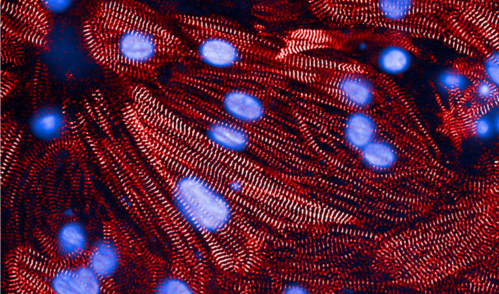

A microscope image of heart muscle cells, with contraction-related proteins stained red and cell nuclei stained blue.

Credit: Anant Chopra, Broad/Bayer Precision Cardiology Lab

Heart muscle cells

Laboratory experiments reinforced the mechanistic pathway: When researchers reduced CD36 protein expression in cultured heart muscle cells using RNA interference, the cells took up less fuel and showed impaired contraction.